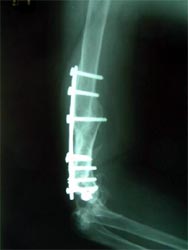

病例三、

肱骨骨不连的骨断端多有硬化而骨干骨质疏松、遗留有以往手术钢丝、

钉孔,骨吸收骨干变细皮质变薄,有严重骨缺损。

带锁髓内钉在骨组织和钉体之间提供较均匀的弹性应力分布,避免钢板内固定时

广泛的软组织剥离,抗旋转作用强于可屈髓内钉,不需外固定,对断端稳定性好